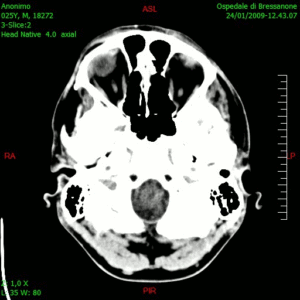

La Clinica Universitaria di Navarra sta reclutando 37 volontari per mettere in pratica quest’idea, applicandola su dei tumori più devastanti: il glioblastoma, malattia cerebrale che colpisce 2.400 persone, di cui solo il 5% sopravvive cinque anni. La tecnica consiste nel produrre vaccini individualizzati.

Non è facile da realizzare. Prima bisogna ottenere cellule sia del tumore sia del sistema immunitario del paziente. Poi devono essere coltivate insieme. In questa fase le cellule responsabili della difesa dell’organismo devono “imparare” a identificare le proteine che indicano la presenza del tumore. In seguito, devono essere re-iniettate nel malato, e bisogna sperare che il sistema immunitario apprenda a rilevare il cancro, ad attaccarlo e a distruggerlo.